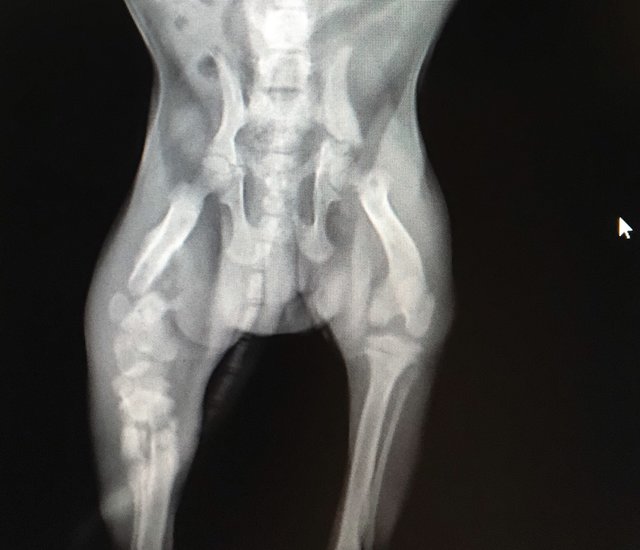

Adorable Pug X Ray: Everything You Need To Know

Adorable Pug Head X Ray l2sanpiero